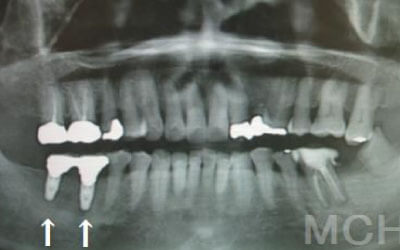

CTでは骨や歯の状態などを3次元で見ることができ、正確な距離を測ることも可能です。

骨の厚みや傾き、神経の位置などを事前にしっかり計測することで安全なインプラントが可能となります。

骨が薄い場合は、そのままインプラントすることはお勧めできません。

ただ、事前に骨を増やす治療をしたり、インプラントと同時に骨を増やす治療をしたりすればインプラントをすることは可能です。

2 神経を傷つけるリスク

顎の骨の中を通っている神経を傷つけるリスクがあります。

ただ、事前にしっかりCT撮影して三次元的に神経までの距離を計測して治療計画を立てれば心配することはありません。

また削りすぎないためのストッパーも当院では使用しております。